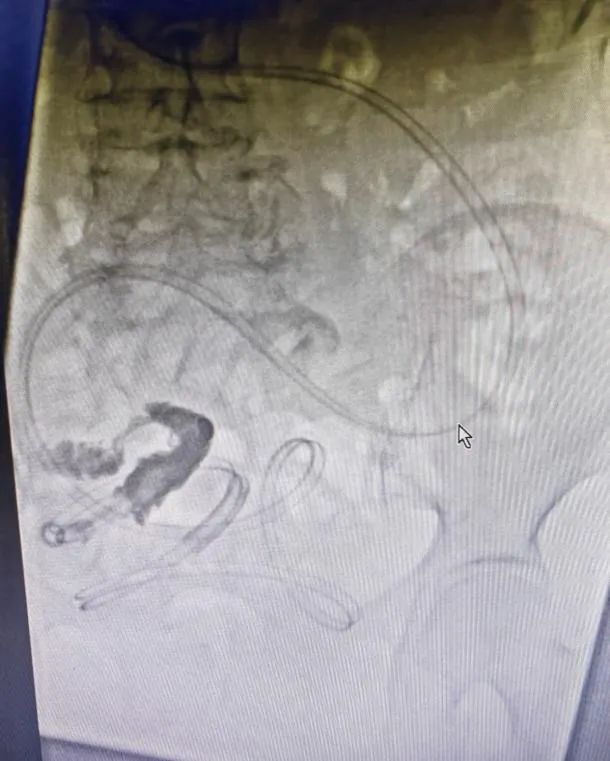

梗阻解除(chú)後複查造影(yǐng)片,見梗阻部位

案例:患者,女,78歲,因“反複腹部脹痛伴肛門停止排(pái)氣排便3年”入院(yuàn),既往有闌尾切除術、輸尿管結石切開(kāi)取石術、輸卵管結紮術(shù)、鼻咽癌放療(liáo)史,有多(duō)次腸梗阻住院(yuàn)保守治療史,結合CT等(děng)檢查,診斷為粘連性腸梗阻,入院後禁食、解痙、抗感(gǎn)染、補液等對症支持(chí)治療(liáo)後,症狀未見明顯緩解,且腹脹逐漸加重,在(zài)DSA下消化道造影及腸梗阻導管置入,術後第二(èr)天梗阻緩解,肛(gāng)門排氣排便(biàn),從而進食,待腸道功能完全(quán)恢複後擇期行腹腔鏡(jìng)下腸粘連鬆(sōng)解術,術後6天(tiān)治愈(yù)出院。

腸梗阻是常見的外科急腹症之一,任(rèn)何原(yuán)因引起的腸內容物通過障礙統稱腸梗阻,其不但(dàn)可引起在腸管形態和功能上的改變,還可導致(zhì)一係列全身性病理生理改變(biàn),嚴重時可危及病(bìng)人(rén)的生命。腸梗阻的治療原則是糾正因腸梗阻所引起的全身生理紊亂和解除梗阻,包括手術治(zhì)療和非手術治療,其中胃腸減壓為(wéi)非手術治療的主要措施之一,傳統的(de)胃腸減(jiǎn)壓(yā)管隻能(néng)放到胃,減(jiǎn)壓效果不夠理想及迅速;而腸梗阻導管是在DSA下通(tōng)過造影判斷解剖及位置,利用導絲、導管技術將減壓管放入小腸,同時通過導管前端水囊的重力及腸蠕動(dòng)作用,將導管推致(zhì)梗阻(zǔ)部(bù)位或者更遠端,從而可快速、精準解(jiě)除梗阻、緩(huǎn)解症狀。同時此技術(shù)的運(yùn)用可避免梗阻不能緩解尤其是粘連性腸梗阻患者的急診手術,通過導管解壓,促進腸道通暢及功(gōng)能恢複,從而擇期選擇腹腔鏡或開放手術解除梗(gěng)阻原因,進一步降低手術風險及並發症的發生,從而達到(dào)縮短住院時間(jiān)及減少創(chuàng)傷的效果。武寧縣人民醫院普外(wài)科已開展DSA下腸梗阻導管置入術,且取得較好療效。